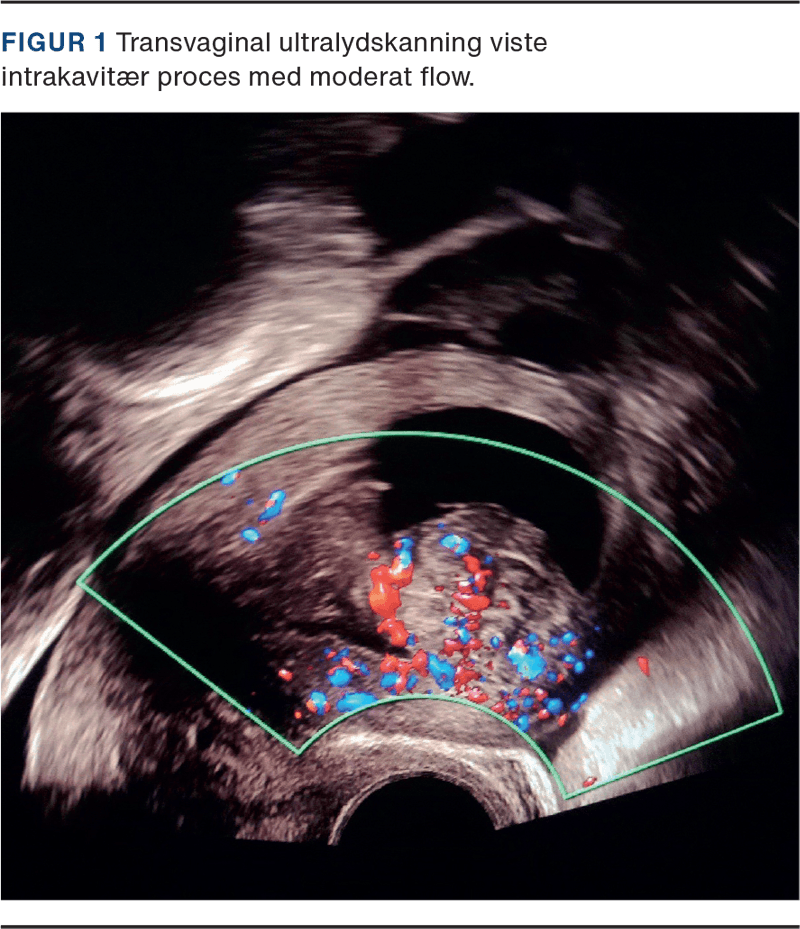

Ved stuegang seks timer senere sås fortsat pågående blødning, som blev estimeret til 600 ml på lejet. Transvaginal ultralydskanning viste moderat flow i den intrakavitære process (Figur 1) og det underliggende myometrium. Rigeligt flow i kombination med kraftig blødning rejste mistanke om sarkom. Man konfererede med onkogynækolog på højtspecialiseret sygehus, som anbefalede at undgå hysteroskopi. Hgb = 4,0 mmol/l efter i alt fem portioner SAG-M, men rotationel tromboelastometri var normal, og der var således ikke længere tale om medicinsk blødning. Der blev givet yderligere to portioner SAG-M og en portion trombocytter. Man forberedte at anlægge en komprimerende ballon i uterus. Patienten blev informeret om, at der ved ukontrollabel blødning var risiko for, at man måtte foretage hysterektomi. Da patienten ikke samtykkede til hysterektomi og på det tidspunkt var transportabel med lægefølge, blev det i samråd med højtspecialiseret sygehus besluttet at udføre akut CT-angiografi og overflytning med henblik på embolisering.